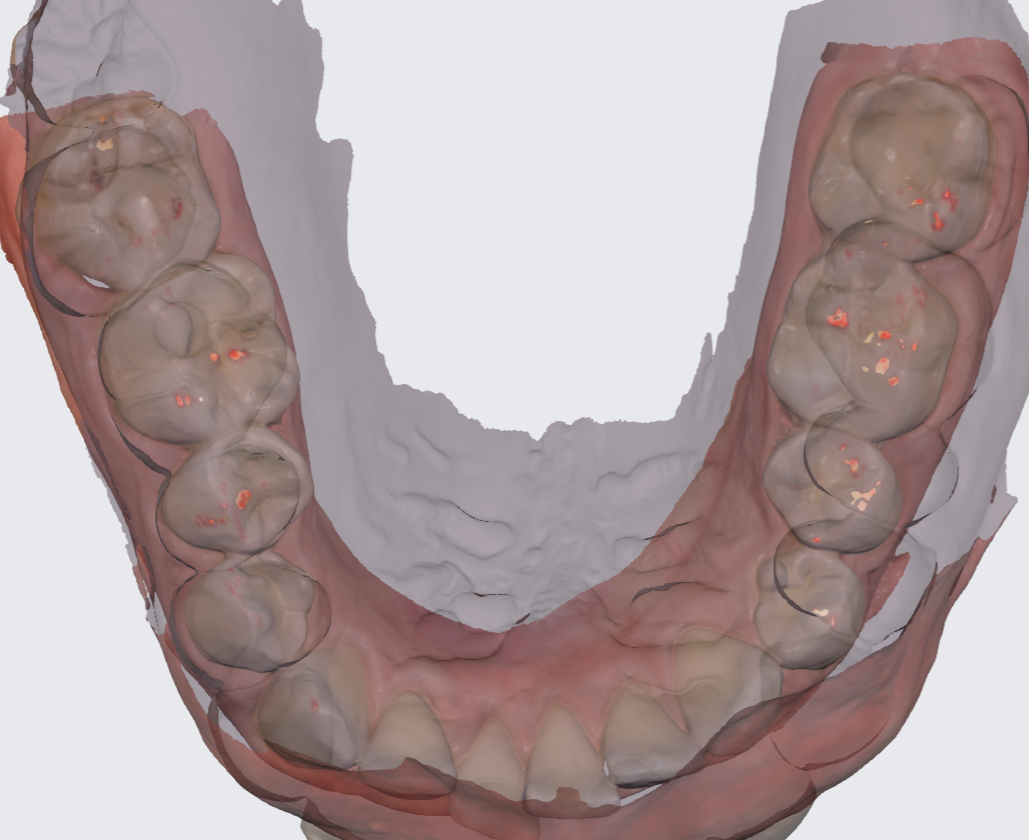

Ieškome odontologės/o 0.5 etato krūviui bpg odontologo darbui. Darbas pobūdis nuo terapijos iki protezavimo. Klinikoje yra 3D rentgenas, 3D skeneris, 3D printeriai, exocad galway modeliavimas, emax keramikos frezavimas, gutta smart, morita zx2, xsmart, propex II. Visos galimybės tobulėti kartu su mūsų komanda. Susidomėjusius skambinti tel. 860612657 arba el.paštu info@dclieporiai.lt